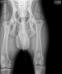

OFA hips and elbows 11.13.18 : SG1 Pyro vom Julianenweg OFA good hips normal elbows 2019 Green Mountain Iron Dog